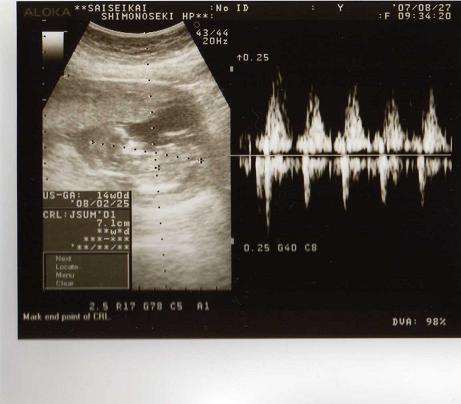

14週目の検診

ベビタンは、7.1cmになってましたよぉ~~

因みに、手も足もちゃんと出来てた~~~(人´▽`*)。;゜☆

足を伸ばせば、ベビタンは10cmにもなるんだとか。

頭の大きさは2.6cm

今日のエコーでは、手足をバタバタ動かしてるのが凄く良く見えたの。